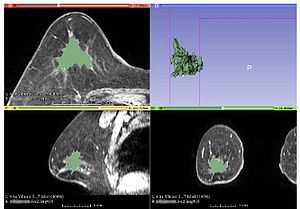

Publication: Sci Rep. 2015 Oct 22;5:15653. PMID: 26489359 | PDF Authors: Ma Z, Chen X, Huang Y, He L, Liang C, Liang C, Liu Z. Institution: Department of Radiology, Guangdong General Hospital, Guangdong Academy of Medical Sciences, Guangzhou, Guangdong, China. Background/Purpose: Accurate and repeatable measurement of the gross tumor volume(GTV) of subcutaneous xenografts is crucial in the evaluation of anti-tumor therapy. Formula and image-based manual segmentation methods are commonly used for GTV measurement but are hindered by low accuracy and reproducibility. 3D Slicer is open-source software that provides semiautomatic segmentation for GTV measurements. In our study, subcutaneous GTVs from nude mouse xenografts were measured by semiautomatic segmentation with 3D Slicer based on morphological magnetic resonance imaging(mMRI) or diffusion-weighted imaging(DWI)(b = 0,20,800 s/mm(2)) . These GTVs were then compared with those obtained via the formula and image-based manual segmentation methods with ITK software using the true tumor volume as the standard reference. The effects of tumor size and shape on GTVs measurements were also investigated. Our results showed that, when compared with the true tumor volume, segmentation for DWI(P = 0.060-0.671) resulted in better accuracy than that mMRI(P < 0.001) and the formula method(P < 0.001). Furthermore, semiautomatic segmentation for DWI(intraclass correlation coefficient, ICC = 0.9999) resulted in higher reliability than manual segmentation(ICC = 0.9996-0.9998). Tumour size and shape had no effects on GTV measurement across all methods. Therefore, DWI-based semiautomatic segmentation, which is accurate and reproducible and also provides biological information, is the optimal GTV measurement method in the assessment of anti-tumor treatments. Funding:

|

MRI-based tumor volume segmentations with the semiautomatic and manual segmentation methods. Tumour segmentation was performed with 3D Slicer v4.3 software. The leftmost images present the same subcutaneous tumor (red arrows) on an axial slice: b = 0 s/mm2 DWI (uppermost), b = 20 s/mm2 DWI (second image from the top), b = 800 s/mm2 DWI (third image from the top), and mMRI MRI (lowest). Moreover, comparison of total tumors in corresponding sequences obtained from semiautomatic segmentation by 3D Slicer (green, middle images) and manual segmentation by ITK (blue, rightmost images) are presented. |